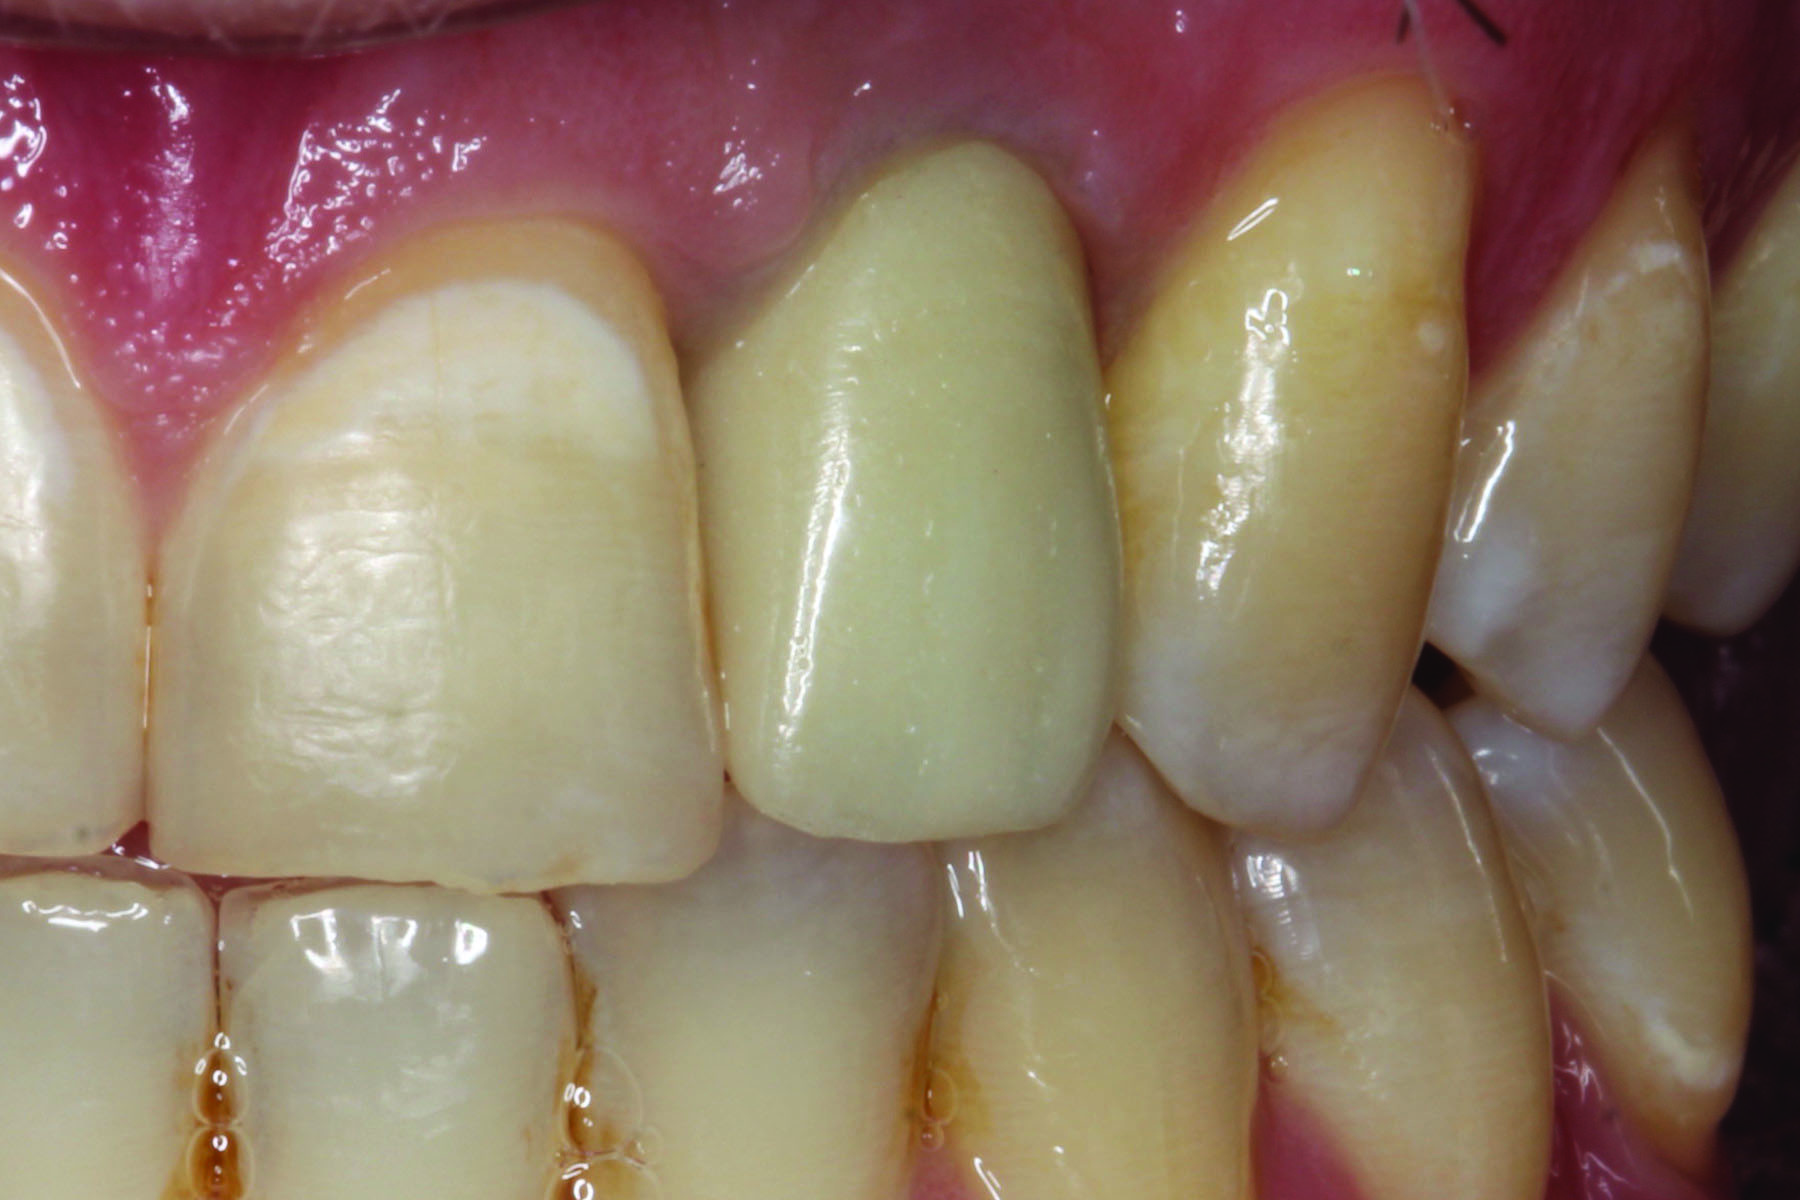

Figure 3 and Figure 4 show a gold anodized abutment and an overlying lithium-disilicate restoration, respectively. Zirconia is a relatively opaque ceramic, and studies are less clear as to the benefit of the use of gold anodized abutments under zirconia implant crowns. One study of 0.7 mm to 1.1 mm thick zirconia specimens reported that gold anodization of a titanium background did not improve the color match to a zirconia crown against a zirconia background.10 On the other hand, another study reported that the color change of 0.5 mm thick zirconia specimens against titanium backgrounds could be improved by gold anodization.11

Fig 3. Gold anodized titanium custom abutment in preparation for crown cementation.

Figure 3

Fig 4. Lithium-disilicate crown cemented over the gold anodized titanium custom abutment shown in Fig 3.

Figure 4